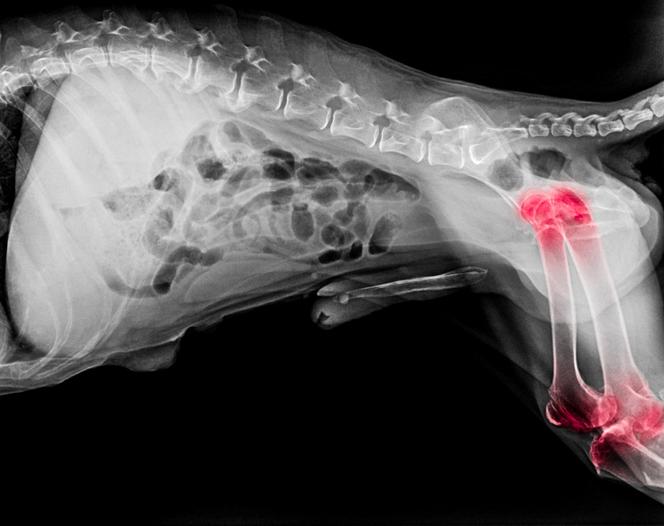

La artrosis es una enfermedad degenerativa y progresiva de las articulaciones, más frecuente en los perros de mayor edad. El cartílago, que recubre y protege las articulaciones, se destruye en los perros con artrosis. Además se produce a su alrededor un crecimiento óseo anormal, de forma que la superficie se muestra irregular, incluso con fragmentos desprendidos. Estos daños pueden verse en las radiografías. Una articulación en este estado permite el roce de las superficies, lo que incrementa la degeneración y causa un dolor considerable que, lógicamente, va a afectar a la movilidad del perro.

Es posible distinguir una artrosis primaria, consecuencia del envejecimiento, y otra secundaria, que es la que aparece tras un factor desencadenante como un traumatismo o una malformación tipo displasia. La obesidad también acaba por dañar las articulaciones y existen enfermedades sistémicas que pueden producir cojeras o degeneración en las articulaciones. En la artrosis primaria suele verse afectada más de una articulación, mientras que la secundaria es más puntual. Con la realización de radiografías el veterinario podrá confirmar el diagnóstico.